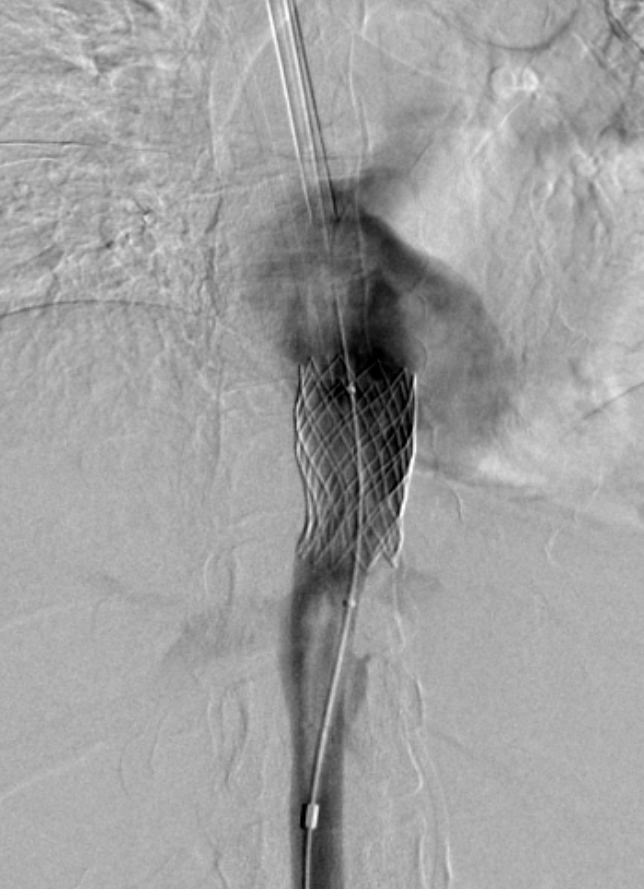

Estenosis vena cava inferior